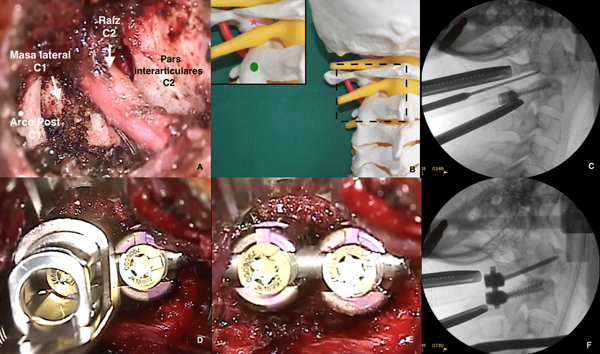

Una vez lograda la exposición ósea deseada (Figura 6A) y localizado el punto de ingreso de los tornillos en la masa lateral de C1 y en la pars interarticularis de C2 (Figura 6B); y antes de proceder con la colocación de los mismos, se deben decorticar las superficies óseas para favorecer la artrodesis con los chips óseos que se colocaran a posteriori, ya que una vez colocado el material protésico no queda espacio suficiente para poder realizar esta maniobra.

Figura 6. Artrodesis instrumentada posterior C1-C2.

A. Exposición intraoperatoria. B. Representación en maqueta del punto de entrada de los tornillos en la masa lateral de C1 (estrella) y en la pars interarticularis de C2 (círculo). C. Radioscopía intraoperatoria durante el fresado de la dirección del tornillo de C1. D. Imagen intraoperatoria: el campo quirúrgico permite la utilización de todos los instrumentos requeridos para la correcta colocación de los tornillos y barras. E. y F. Imagen final intraoperatoria de la lodge (E.) y de radioscopía (F.) con los tornillos y barras colocadas.

Artrodesis instrumentada

A continuación, se colocan los tornillos poliaxiales en C1 y C2 según la técnica de Harms (Figura 6C-F), utilizándose tornillos con rosca parcial o vástago en C1 y teniendo en cuenta que para lograr la trayectoria adecuada en el tornillo del axis, es necesario angular levemente el separador hacia cefálico. La artrodesis se completa con la colocación de la barra y sustituto óseo lateral a la misma.

El procedimiento se realiza con guía radioscópica solo en el plano sagital.